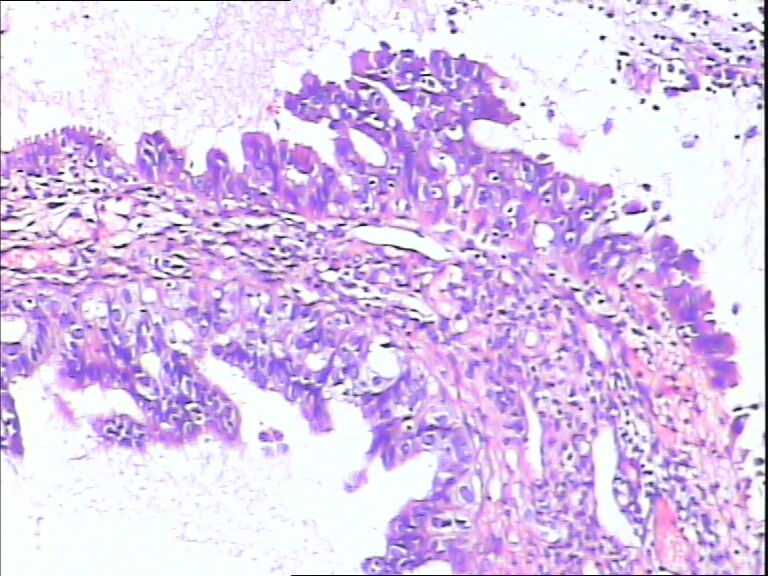

女,43y

左输卵管积液

输卵管长4.5cm;直径:0.8cm

• 请教:输卵管!图2

图2

输卵管增生性上皮病变。

慢性炎伴上皮增生

良性,炎症改变

考虑炎症